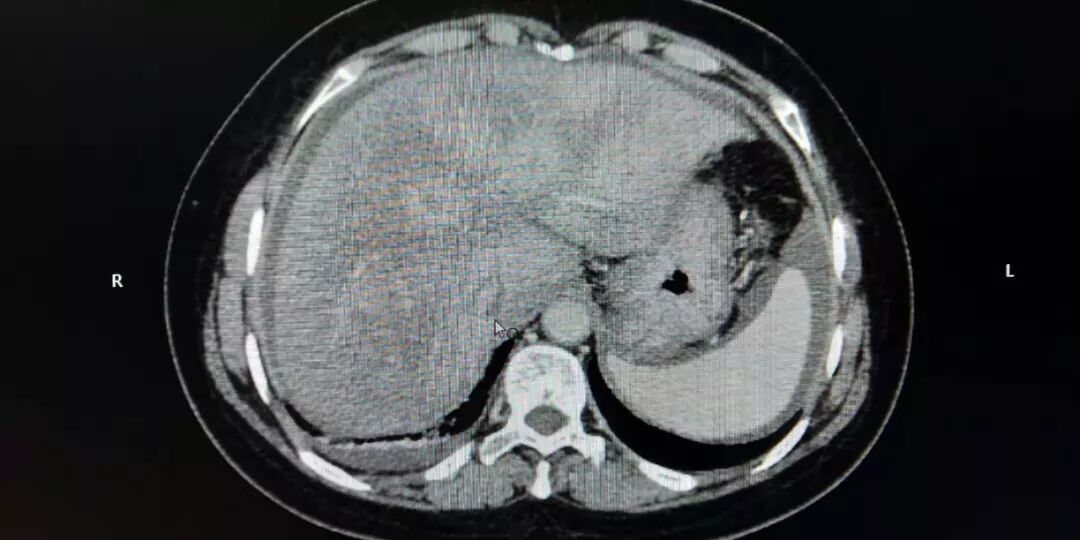

根据患者临床检查和病史,在排除肝前肝后型门脉高压后,内科团队确定患者为肝性门脉高压。同时排除常见的先天遗传及后天获得的如:病毒性肝炎、自身免疫性肝病等原因引起的肝硬化。结合增强CT典型的肝脏不均匀的灌注,呈典型的花斑样改变,同时有大量服用中草药长达一年的病史,由肝小静脉闭塞症所致的门脉高压症,诊断基本成立。